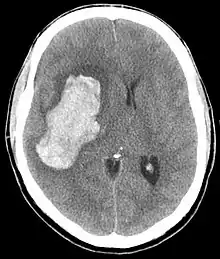

CT scan depicting intracranial hemorrhage, a possible complication of hypertensive emergency. Patients with spontaneous intracranial hemorrhage present with newfound headache and neurologic deficits.

The most common presentations of hypertensive emergencies are cerebral infarction (24.5%), pulmonary edema (22.5%), hypertensive encephalopathy (16.3%), and congestive heart failure (12%).[4] Less common presentations include intracranial bleeding, aortic dissection, and pre-eclampsia or eclampsia.[5]

In the brain, hypertensive encephalopathy - characterized by hypertension, altered mental status, and swelling of the optic disc - is a manifestation of the dysfunction of cerebral autoregulation. Cerebral autoregulation is the ability of the blood vessels in the brain to maintain a constant blood flow. People with chronic hypertension can tolerate higher arterial pressure before their autoregulation system is disrupted. Hypertensives also have an increased cerebrovascular resistance which puts them at greater risk of developing cerebral ischemia if the blood flow decreases into a normotensive range. On the other hand, sudden or rapid rises in blood pressure may cause hyperperfusion and increased cerebral blood flow, causing increased intracranial pressure and cerebral edema, with increased risk of intracranial bleeding.[6]

Consequences of hypertensive emergency result after prolonged elevations in blood pressure and associated end-organ dysfunction. Acute end-organ damage may occur, affecting the neurological, cardiovascular, kidney, or other organ systems. Some examples of neurological damage include hypertensive encephalopathy, cerebral vascular accident/cerebral infarction, subarachnoid hemorrhage, and intracranial bleeding. Cardiovascular system damage can include myocardial ischemia/infarction, acute left ventricular dysfunction, acute pulmonary edema, and aortic dissection. Other end-organ damage can include acute kidney failure or insufficiency, retinopathy, eclampsia, lung cancer, brain cancer, leukemia and microangiopathic hemolytic anemia.